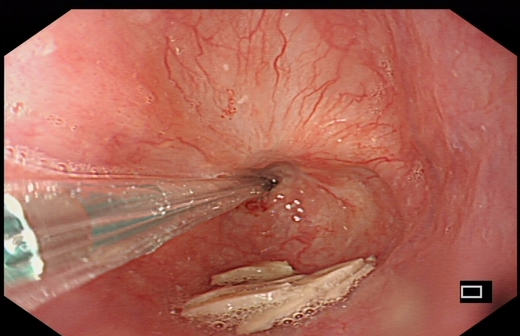

球囊扩张治疗中

X线透视下球囊扩张中